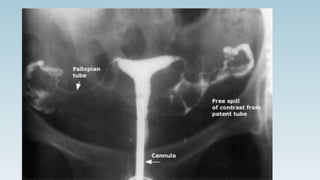

HYSTEROSALPHINGOGRAPH

Y (HSG)

Operative procedure to assess interior anatomy of uterus and

tubal patency

INDICATIONS

1. ASSESS INTERIOR ANATOMY OF UTERINE

-Detection of Uterine malformations

-Diagnosis of cervical in competence

-Detection of translocated IUD

-Diagnosis of uterine synechiae

-Confirm diagnosis of secondary abdominal pregnancy

2. TO ASSESS TUBAL PATENCY

-Following tuboplasty

PROCEDURES

1. Ask patient to empty bladder

2. Position: dorsal position with buttocks on the edge

3. Do internal examination

4. Introduce posterior vaginal speculum

5. Held anterior lip of cervix with Allis forceps

6. Introduce uterine sound to see length and direction of

uterine cavity

7. HSG cannula fitted with syringe is introduced. (fill syringe

with 5-10 ml of dye)

8. Inject dye slowly

9. Passage of dye into interior is observed by X-ray intensifier